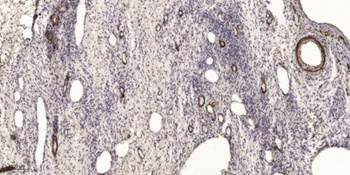

Immunohistochemical analysis of PENK staining in human testis formalin fixed paraffin embedded tissue section. The section was pre-treated using heat mediated antigen retrieval with sodium citrate buffer (pH 6.0). The section was then incubated with the antibody at room temperature and detected using an HRP conjugated compact polymer system. DAB was used as the chromogen. The section was then counterstained with haematoxylin and mounted with DPX.